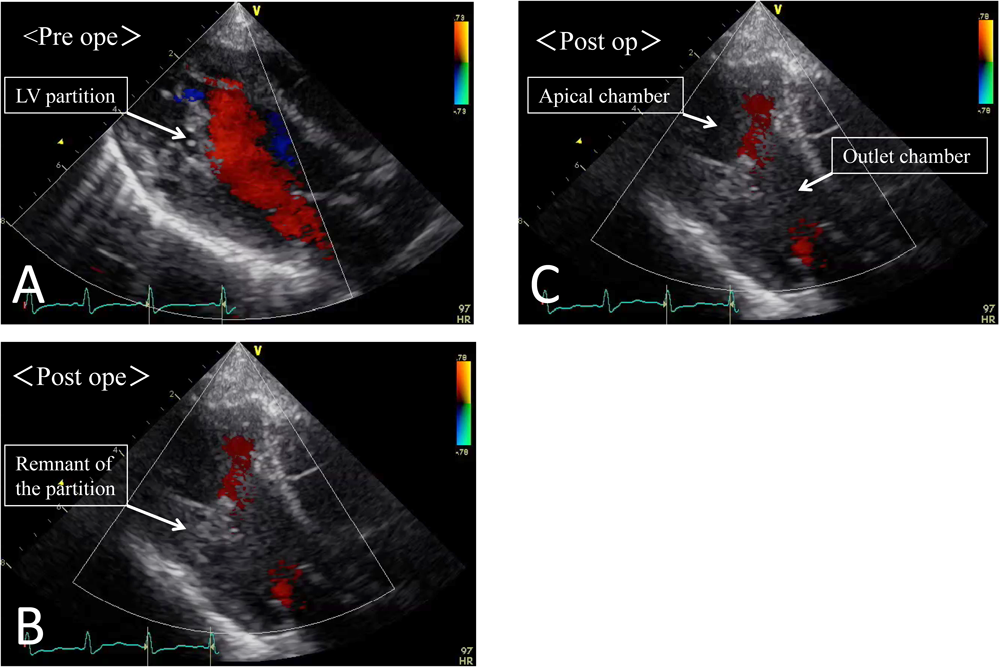

頭部MRIにて左中大脳動脈領域の血流途絶と同領域の脳梗塞を認めた.心エコーでは左室隔壁で隔てられた左室心尖部の動きは良好であり血栓を認めなかった(Fig. 1A*).脳梗塞に対する治療経過中,入院10日目の心エコーで左室心尖腔に11×10 mm大の血栓形成,心尖腔の機能低下と主腔との交通狭小化が見られた(Fig. 1B*).これらの血栓飛散による臓器梗塞,および機能低下による血行破綻を回避する目的で緊急手術を行った.

Pediatric Cardiology and Cardiac Surgery 32(1): 38-42 (2016)

Fig. 1 Preoperative echocardiography

A: At admission. B: 10 days after admission.

第1病日に抜管した.左室副腔機能は速やかに改善し,神経学的所見の悪化もなく,第27病日に軽快退院した.術後9ヶ月時の心エコー上,左室副腔機能は良好に維持され血栓や僧帽弁逆流を認めていない(Fig. 3*).自発運動に左右差を認めず歩行可能となっている.

Fig. 3 Perioperative echocardiography

A: Preoperative echo showed a narrow communication between the two chambers of the left ventricle. B: Echocardiography 1 week after surgery. C: Echocardiography 9 months after surgery showed a wide communication similar to that seen at immediately after surgery.